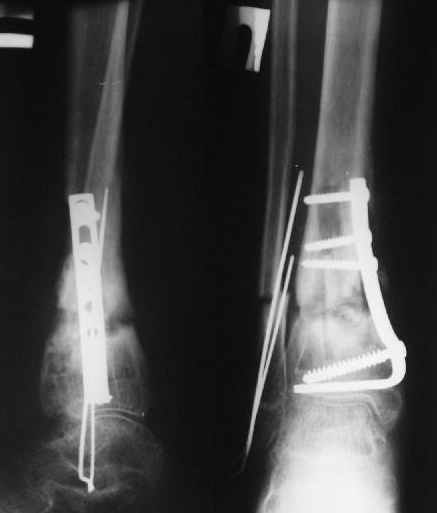

Операции: 1 Клиновидная резекция на вершине деформации м\берцовой кости.

2 Тугоподвижный ложный сустав н\3 б\берцовой кости. Рубцы выполняющие пространство между отломками, канал проксимального отломка иссечены.

Одномоментное устранение деформации, остеосинтез Г-образной пластиной.

Пластика по Хахутову.

Заживление проксимальной части раны вторичным натяжением без нагноения. Рана зажила. Спицы удалены через 1,5 недели после операции.

Особого смысла в них не было.

Учитывая фон (интеллект, etc) гипсовая повязка.

На данный момент ходит при помощи костыля (без присмотра -без костыля :), разрабатывает движения в г\стопном суставе.

Фиксация

в гипсе